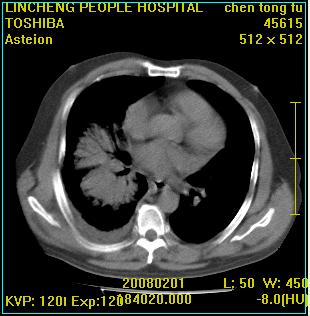

患者,男性,62岁。主因头晕,发热,咳嗽6天,高热达39度,esr19mm/h,wbc 3.9×10 9/l

大叶性肺炎并胸膜炎

右肺大叶性肺炎,胸腔积液。建议痰检。

实变区见空气支气管征,支气管通畅,考虑为大叶性肺炎,右侧少量胸水

1)考虑为:右肺感染性病变。建议:抗炎治疗复查。2)右侧少量胸腔积液。

考虑为右肺大叶性肺炎,胸腔积液,建议必要时纤维支气管镜检查,以排除肿瘤性病变。

右肺炎症并右侧胸腔少量积液。

大叶性肺炎并胸膜炎、胸水。

考虑为右肺大叶性肺炎伴少量胸腔积液,建议复查,如病变不吸收或吸收不明显,建议纤维支气管镜检查,除外细支气管肺泡癌的可能。

右侧大叶性肺炎,右侧少量胸腔积液.

实变区见空气支气管征,支气管通畅,考虑为大叶性肺炎,右侧少量胸水。